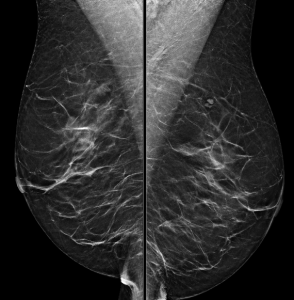

A 48-year-old woman presents for screening mammogram:

How do you best describe the patient’s breast density?

A. The breasts are almost entirely fatty

B. There are scattered areas of fibroglandular density

C. The breasts are heterogeneously dense

D. The breasts are extremely dense

Answer

Either B. There are scattered areas of fibroglandular density, or C. The breasts are heterogeneously dense

Explanation: One of the first steps in interpreting a mammogram is assessing the breast composition, also known as breast density. There are four acceptable categories described in the BI-RADS manual, which are listed above. Breast density is a subjective assessment of how much fibroglandular tissue compared to fat tissue is present in the breast, and also has a correlation to how difficult it may be to interpret a patient’s mammogram. Woman who have “dense” breasts (heterogeneously or extremely dense) have a slightly increased risk of developing breast cancer compared to women with non-dense breasts. This patient’s breasts were reported as being composed of scattered areas of fibroglandular density. Since this is a subjective determination, describing them as heterogeneously dense could also be acceptable.